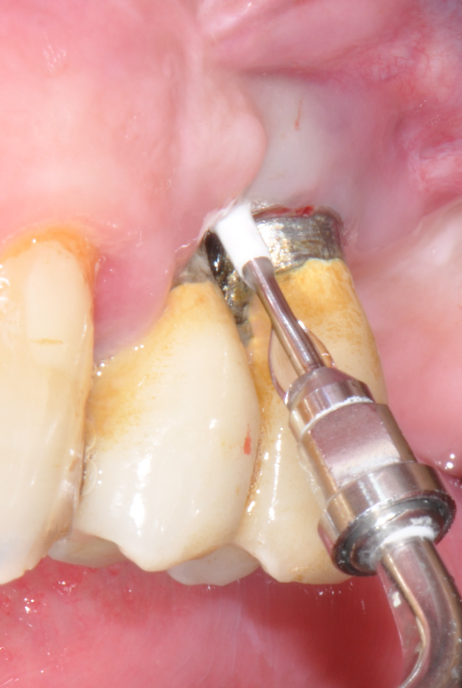

Fig.7: Pocket decontamination with erythritol powder conveyed by sub-gingival tip.

So far, there is no scientific evidence supporting the efficacy of this coadjuvant. The tested protocol consist of a Multiple Anti Infective Non Surgical Therapy (MAINST) that involves the use topical 14% doxycycline to solve the peri-implantitis acute phase and, after 7 days, a session of Full Mouth Air Polishing Therapy (FM-EPAPT) through erythritol powder (Fig.7), a piezo-ceramic device with a PEEK tip (Fig.8), the curettage of internal pocket line (Fig.9) and a second application od Doxy. The patients were further followed with quarterly maintenance sessions carried on with the same FM-EPAPT protocol. Up to 12 months BOP and mean PD decreased significantly and successfully, accompanied by a gain of attachment level up to 12 months. The first case-series about MAINST is waiting to be published and the results are encouraging. Figure 10 and 11 show the healing at 6 and 12 months after MAINST protocol of the peri-implantitis case displayed at the beginning of this article (Fig.1,2,3,4) and figure 12-21 show a complete MAINST case.